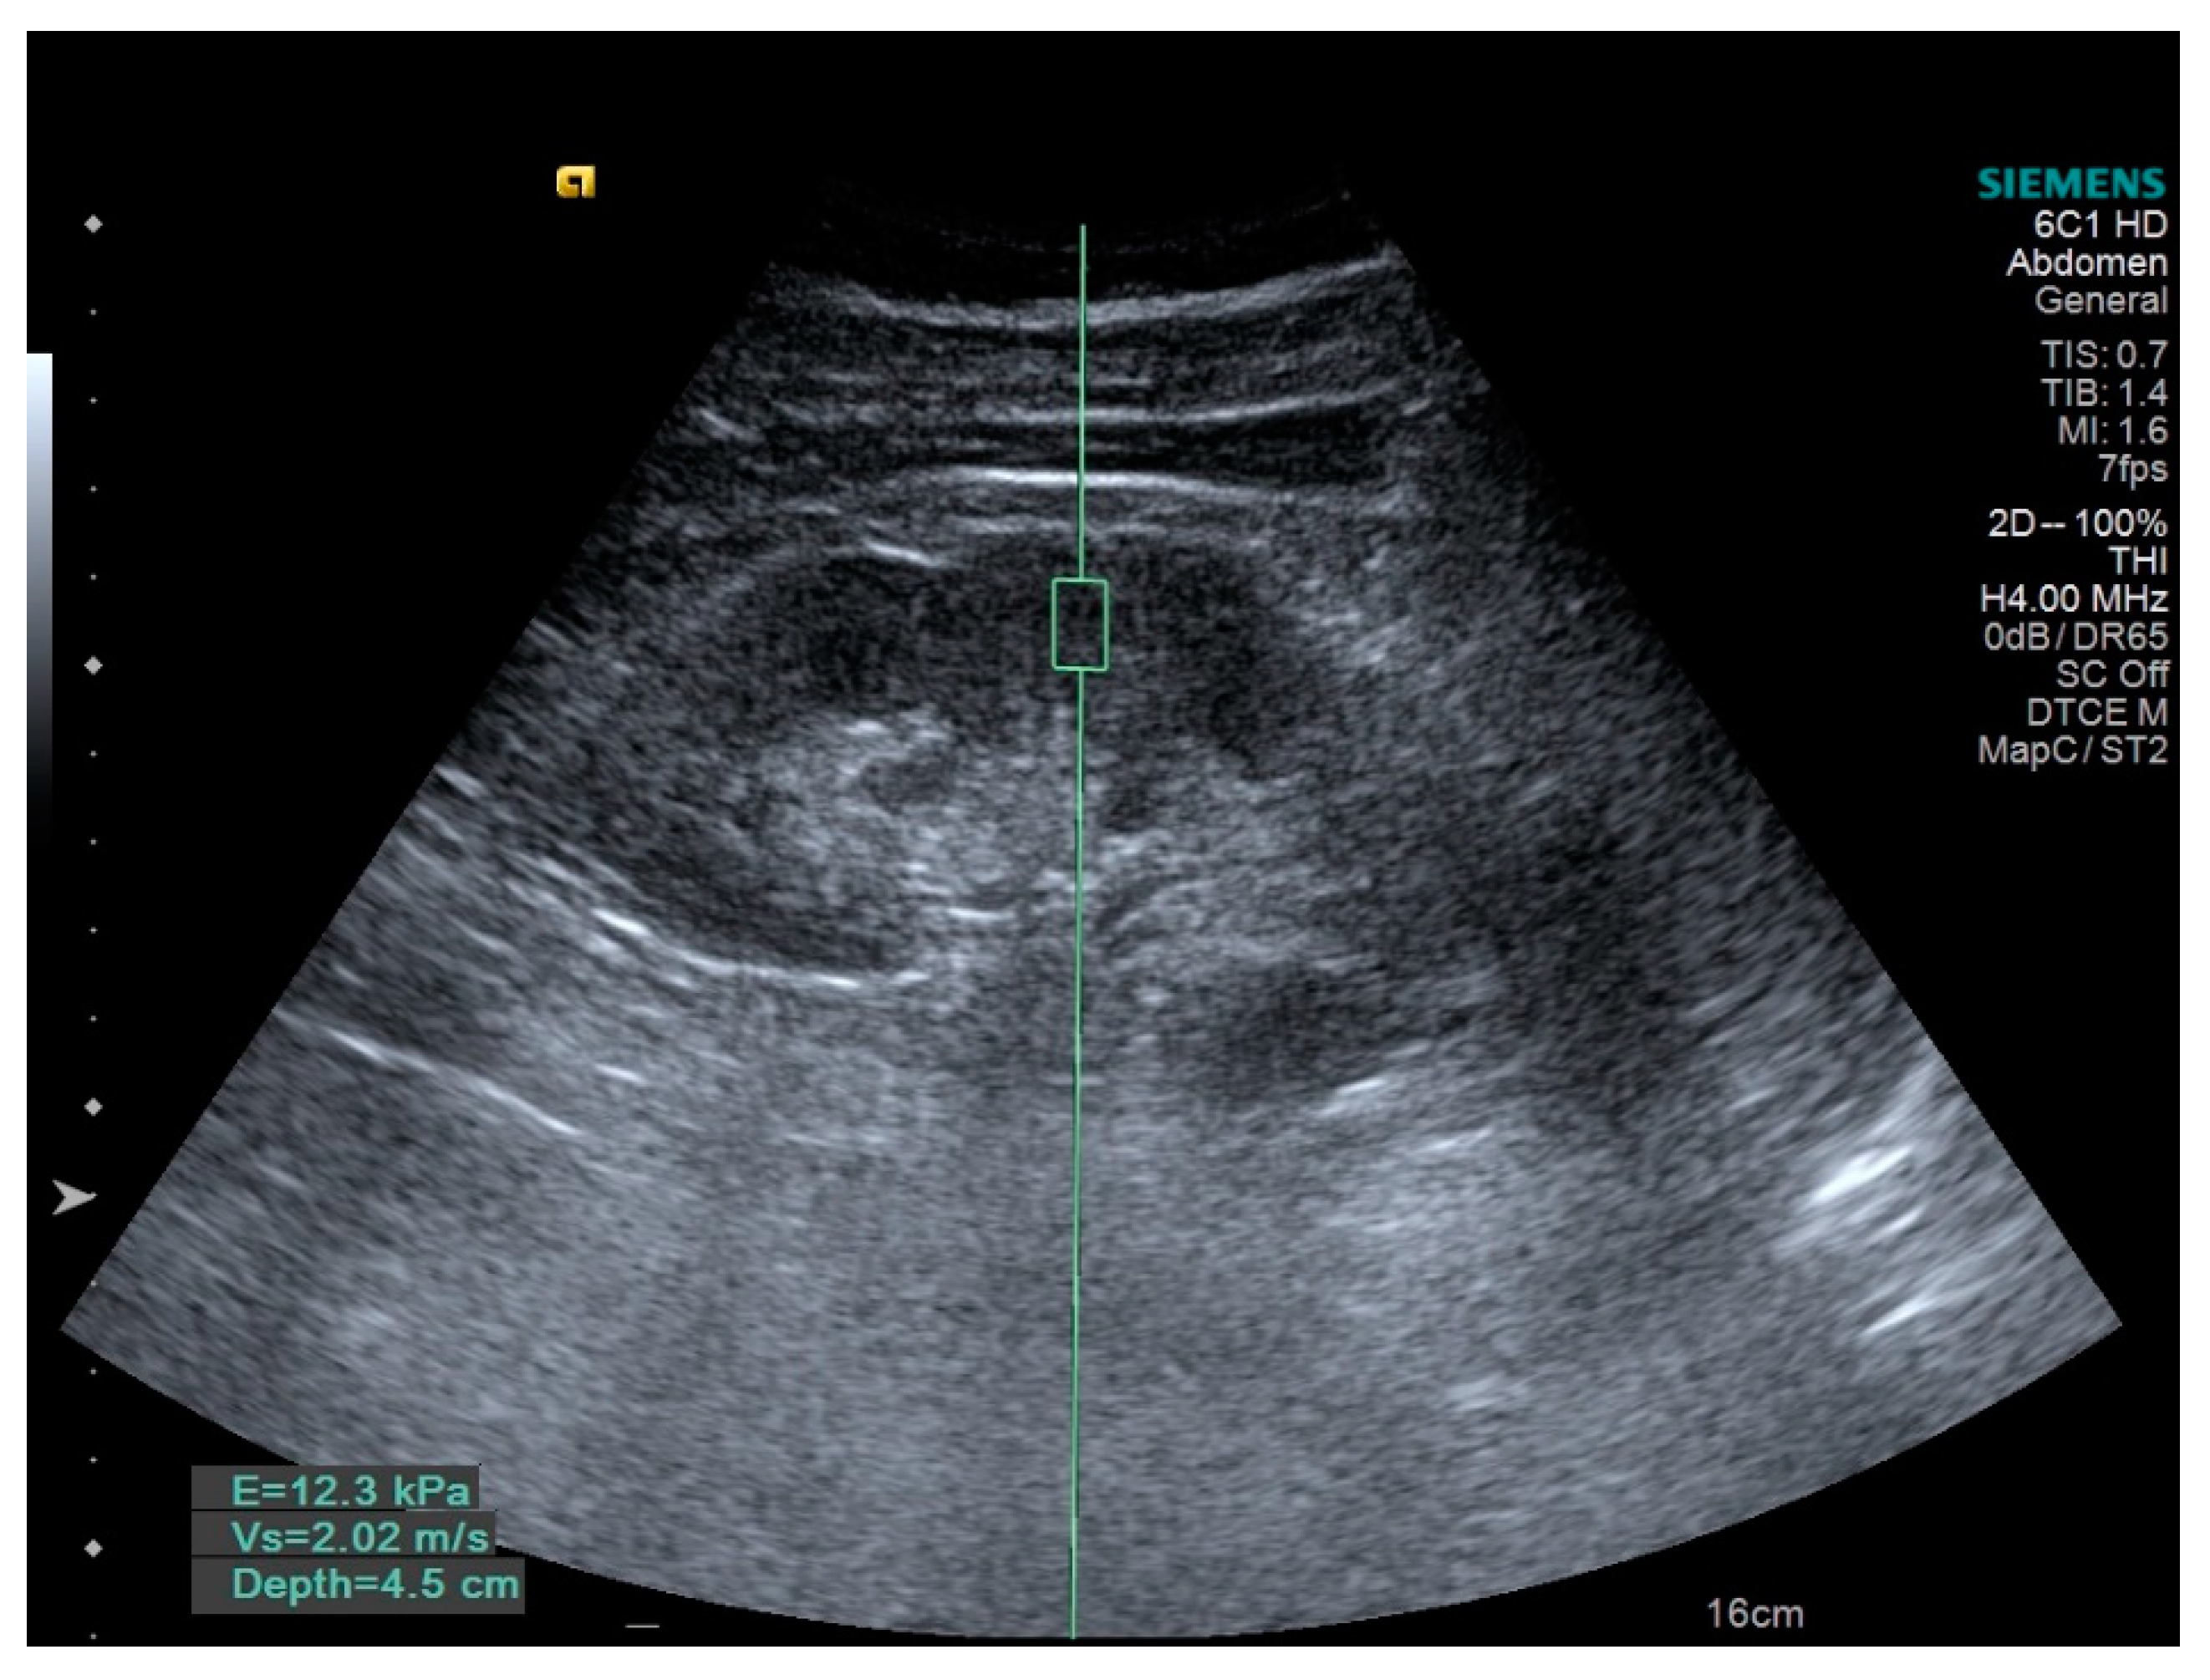

The histological abnormalities are responsible for the changes of the monitored parameters. Intrarenal parenchyma arteries show progressive intimal thickening, afferent arterioles present a process of arteriosclerosis, all these changes being highlighted by the increase of RRI (Figure 1). Another factor responsible for the RRI increased is tubular atrophy associated with interstitial fibrosis [9,20,21]. Glomerular involvement is expressed by UACR increasing [9]. But the kidney is a complex organ and the SWV, as a marker of its stiffness, is dependent on the degree of renal fibrosis, as well as on the intrarenal vascularization [22] (Figure 2).

ARFI uses short-duration acoustic radiation forces that produce localized displacements in the renal tissue [31,32]. The renal shear wave velocity (SWV) represents the speed of a transverse wave that propagates perpendicular to the direction of tissue movement, which is a representative factor of renal tissue rigidity [33,34]. Renal elasticity changes during the HN progression. The speed of shear wave propagation is measured and is proportional to the stiffness of the renal tissue [22,32,33]. In the present study the SWV values were between 1.82 and 2.99 m/s. The studied HN patients presented low values of SWV than the controls (2.37 ± 0.34 m/s in HN patients, versus 2.96 ± 0.18 m/s in controls), statistically significant (p < 0.0001). Guo et al. and Zheng et al. reported similar results (p < 0.001, respective p < 0.05) [34,35]. Munger et al., based on the fact that 20% of cardiac output enters the kidneys, and that changes in this flow affect renal function, has shown that renal SWV is dependent on intrarenal vascularization [36]. Bob et al., in their study, demonstrated that renal SWV depends not only on renal fibrosis, but also on intrarenal vascularization [22]. Under HN conditions, reducing the diameter of the intrarenal vessels leads to a reduction in blood flow, and then, SWV [35].

Figure 2. ARFI; SWV = 2.02 m/s.